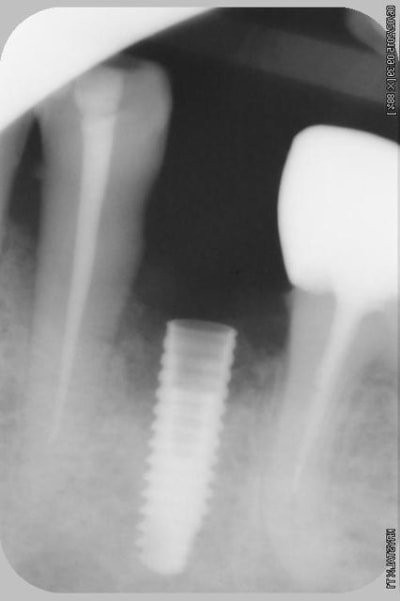

alors là pas du tout, le patient vient me voir pour des implants, donc je fais une étude du cas absence des molaires supérieures, couronnes mandibulaires très ancienne 45 racine cassée, 44 dévitalisée mais passablement déchaussée, donc avulsion de 45 et pose d'un implant avant de refaire les couronnes 46/47 et l'ensemble.

Échec implantaire, et oui ça arrive, même dans un cas paraissant simple.

Oui, un Px, le premier était un Reg.

l'os était tendre, ce qui explique le choix du Px